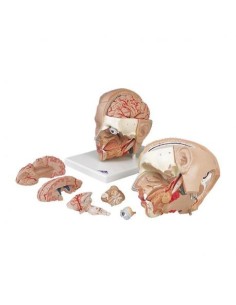

Crâne classique transparent, séparable en 3 parties, modèle anatomique 3B Scientific A20/T

3B scientifique, enseignement de luxe crâne BONElike™A283

Du crâne en 22 parties à verrouillage magnétique aux modèles de colonne vertébrale, des modèles d'articulation aux modèles de cœur, chaque pièce de notre collection est conçue pour une immersion totale dans l'étude de l'anatomie humaine. Nos modèles, réalisés à partir de scans d'os réels, garantissent une expérience tactile authentique et une fidélité de poids presque identique aux originaux.